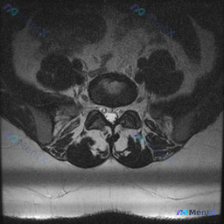

今天分享一个很值得思考的病例,不是病例本身复杂,而是考验我们面对不合格检查结果的处理思路——需求是分析这张腰椎MRI T2轴位的椎间盘病变,我们先看影像分析结果: 一、基本影像情况 这是一张腰椎MRI T2序列轴位图,整体存在非常明显的伪影,严重干扰了图像对比度、分辨率和解剖结构清晰度,图像边缘模糊...

病例影像分析:临床怀疑椎间盘病变,单张腰椎MRI表现分享 整理了一份影像会诊病例,临床方向是排查椎间盘病变,分享一下完整分析思路。 影像基本信息 本次分析为单张腰椎MRI T2序列轴位图像,定位为腰椎中下段水平。 影像结构评估结果 椎体与椎间盘 - 椎间盘(髓核)信号呈中等强度,未见显著严重脱水(低...